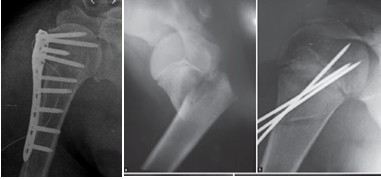

* Phương pháp

- Kết xương nẹp vít:

- Xuyên đinh Kirschner